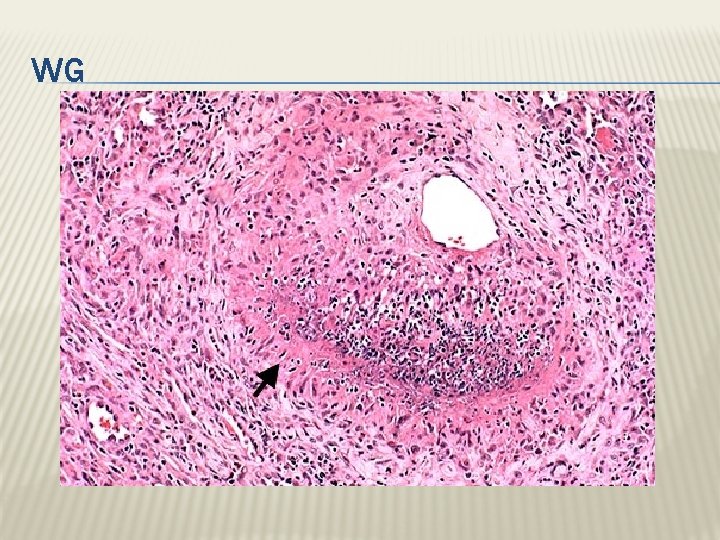

WEGENER GRANULOMATOSIS is a necrotizing vasculitis characterized by the triad of 1) necrotizing granulomas of the upper and lower respiratory tract 2) necrotizing or granulomatous vasculitis of small to mediumsized vessels 3) renal disease in the form of necrotizing, crescentic, glomerulonephritis.

WG